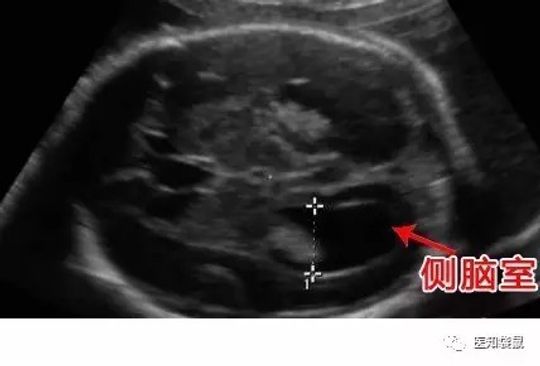

4、轻度侧脑室增宽

正常情况下,侧脑室宽度应在10 mm以内,如果宽度达到10~15 mm之间时,则称为轻度侧脑室增宽。

轻度侧脑室增宽可发生在健康胎宝宝的身上,但这种概率较低,通常仅为0.15%。侧脑室增宽的发生多与胎儿染色体异常有关,其中以21-三体综合征最为多见,发病率为1.4%,是普通胎儿的9倍,而且宝宝日后发生神经系统发育异常的可能性会增加10%~30%。

所以,一旦发现胎儿侧脑室增宽,医生会仔细检查胎儿的结构,并建议准妈妈进行羊膜腔穿刺,以及筛查胎儿感染的指标,必要时还要做胎儿神经系统MRI检查,以排除胎儿是否合并有颅内其他发育异常,例如胼胝体发育不良或脑室系统梗阻等。

侧脑室增宽的程度不同,预后也是不一样的。研究显示,侧脑室扩张宽度为10.0~12.0mm的宝宝预后较好。